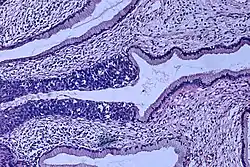

High-grade dysplasia (carcinoma in situ) in the uterine cervix: The abnormal epithelium is extending into a mucous gland to the left of center. This disease can progress to invasive cancer (squamous cell carcinoma) of the cervix.